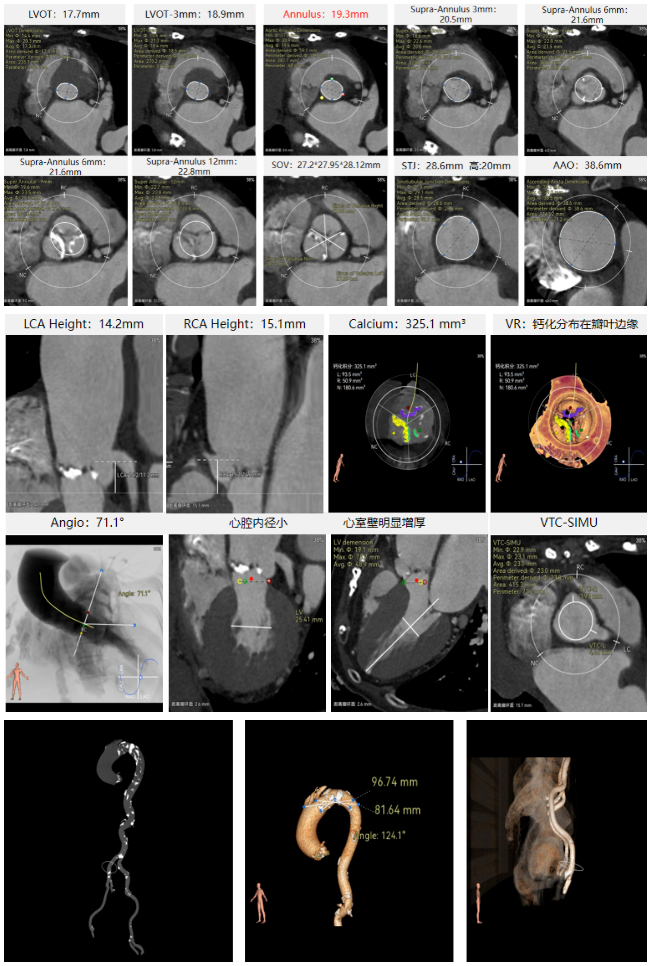

刘煜昊教授 阜外华中心血管病医院(点击查看专家详细简历) 首瓣选耐久,干瓣护航全生命周期管理 2025年ESC专家共识里指出:“推荐第一个瓣膜要选经证实具有长期耐用性的外科瓣膜与经导管瓣膜,以降低再次介入治疗的可能性 ,对于瓣环较小、根据预测有效瓣口面积(EOA)评估存在严重 PPM 风险的患者,可采用主动脉根部扩大术联合 SAVR,或植入环上瓣,对于小瓣环患者自展瓣拥有比较好的血流动力学优势”。 每一次术前评估,都是我们与患者携手面对未知的起点。我们始终以患者全生命周期获益为核心,在瓣膜选择与术式规划中,不只着眼于当下解剖适配,综合评估解剖条件、预期寿命与生活质量。从年轻患者到高龄人群,瓣膜耐久性与血流动力学稳定性始终是决策核心! 陈同峰教授 阜外华中心血管病医院(点击查看专家详细简历) 医学的进步正不断拓宽生命的边界,每一次术前评估都是对生命尊严的深度凝视,技术与人文的交融,让风险不再仅是数字的堆叠,而是成为医者与患者共同面对未知的勇气见证。术中瓣膜释放结束,到了导管测压的时候,我惊喜:瓣膜不错啊,压差为0,这不仅仅得益于瓣膜形态的设计,更是环上瓣及瓣叶材质优质的体现,感受到了 Prostyle A瓣膜在血流动力学上的卓越表现,其采用的抗钙化处理技术有效延长了瓣膜的耐久性,为患者长期生存提供了更可靠的保障。 患者病史 主诉:心慌半月; 门急诊诊断:心悸,冠状动脉粥样硬化性心脏病,心脏瓣膜病,主动脉瓣狭窄,高血压,甲状腺术后; 现病史:半月前无明显诱因出现心慌,呈间断性,伴心悸、出汗,伴头晕,无咳嗽、咳痰,无恶心、呕吐,无双下肢水肿,无放射痛及意识障碍,休息约几分钟后可自行缓解,症状反复发作,遂来我院就诊。 术前超声提示:室间隔增厚;主动脉瓣退行性变并重度狭窄;升主动脉明显增宽;室间隔增厚。 术前CT 三叶瓣,轻度钙化集中在无窦和左窦瓣叶边缘,主动脉根部直径19.3mm,LVOT直径17.7mm,LVOT向下收窄; 窦部正常,VTC空间足够,冠脉风险低; 左室腔小,收缩末径20-25mm,“自杀左室”,循环崩溃风险高;主动脉瓣环水平夹角71.1°,横位心,过弓和跨瓣存在一定困难,备snare。 外周双侧入路内径可,双侧入路能够支持20F大鞘通过,右股低分叉。 手术策略 推荐右侧股动脉为主入路,左侧为辅助入路,右股分叉上方1cm穿刺;推荐选择AV23瓣膜,18mm球囊预扩,左右重叠位:LAO 7° CAU 35°;左冠切线位:LAO 27° CRA 16°;右窦居中位:LAO 18° CAU 9°;备Snare,建议ECMO/CPB湿备,术前术中积极补液,警惕循环崩溃风险。 手术过程 在右股动脉穿刺建立通路后,顺利送入大鞘,经食道超声及血管造影确认路径稳定。18mm球囊预扩过程中,患者血压一度下降,迅速完成扩张并立即植入AV23 ProStyle A®瓣膜。瓣膜精准释放于目标位置,超声显示无明显反流及瓣周漏,血流动力学即刻改善。 主动脉根部造影 18mm球囊预扩少量反流 输送系统柔顺跨瓣 精准定位 平稳释放 80%工作位观索位置合适 释放后导管测压,压差由术前53mmHg降为0mmHg 最终造影瓣膜位置形态良好,冠脉灌注良好,无明显瓣周漏 ProStyle A®预装干瓣——助力临床最优化解决方案: 轻松过弓,精准可控:该病例为横位心,在未使用snare的情况下,过弓和跨瓣柔顺,较细的尺寸+柔顺的输送系统通过性能得到了很好的验证; 平衡的收腰设计:该病例瓣环较小且左室腔小,AV23瓣膜的平衡收腰设计既确保了锚定安全性,又保证了EOA,有效降低了循环崩溃风险,而术后0mmHg的压差的表现更加证明了优秀的血流动力学,提高了瓣膜的耐久性; 预装干瓣 便捷顺安:金仕生物专利抗钙化技术运用纳米技术去除组织内的细胞碎片和磷脂,封闭游离醛基,从根本上阻断了瓣膜钙化的多项因素,显著提升了瓣膜的耐久性;同时,相比较传统戊二醛保存方式,干式存储最大限度的保留心包的亲水亲油平衡,还原组织天然曲柔性,进一步保障了瓣叶开合,保证长期耐久性。 专家简介 王小虎 阜外华中心血管病医院(点击查看专家详细简历) 陈冲 阜外华中心血管病医院(点击查看专家详细简历) 赵一品 阜外华中心血管病医院(点击查看专家详细简历)